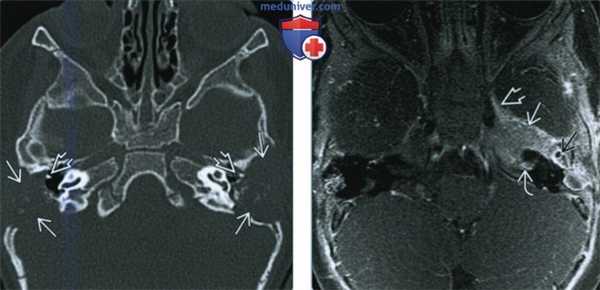

(Слева) При аксиальной КТ в костном окне у двухлетней девочки с двухсторонней отореей определяются хорошо отграниченные деструктивные поражения (ЛКГ) сосцевидного отростка и чешуи височной кости с обеих сторон. Снижена пневматизация полости среднего уха с обеих сторон на фоне практически полной деструкции слуховых косточек. Агрессивная периостальная реакция, типичная для метастатической нейробластомы, в этом случае не выражена.

(Справа) При аксиальной МРТ Т1 С+ FS определяется ЛКГ с накоплением контраста и распространением в среднюю черепную ямку, кавернозный синус, внутренний слуховой канал. Слуховые косточки погружены в опухоль.

2. КТ при лангергансоклеточном гистиоцитозе височной кости:

• КТ в костном окне:

о Различные литические «штампованные» поражения:

- Обычно с «географической» деструкцией сосцевидного отростка и/или чешуи височной кости

- Возможно поражение вершины пирамиды, слуховой капсулы, ± слуховых косточек

о Литические поражения со скошенными краями:

- Чаще в своде черепа

- Также возможны склеротические изменения (чаще в основании черепа)

о Возможна диффузная деструкция височных костей